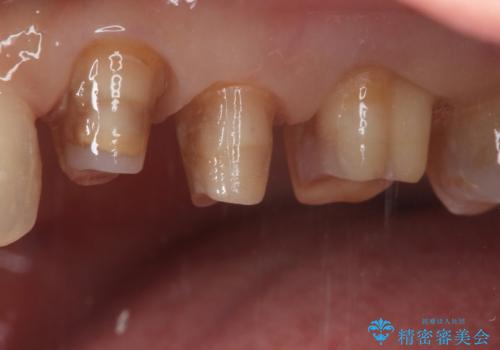

- 定期健診にて虫歯が見つかった患者さんです。県外からお越しいただいている事もあり、かなりお久しぶりの来院でした。歯と歯の間のところと銀歯の下が虫歯になっていました。被せ物はオールセラミッククラウンで治療しました。

銀歯を外すとかなり大きな虫歯になっていました。幸いぎりぎりのところで神経まで虫歯は広がっていなかったため、症状が出ない事を確認した後、オールセラミッククラウンで治療しました。虫歯除去後、残っている歯質が少なかったため、破折抵抗を考慮し部分的な被せ物ではなくクラウンを選択しました。